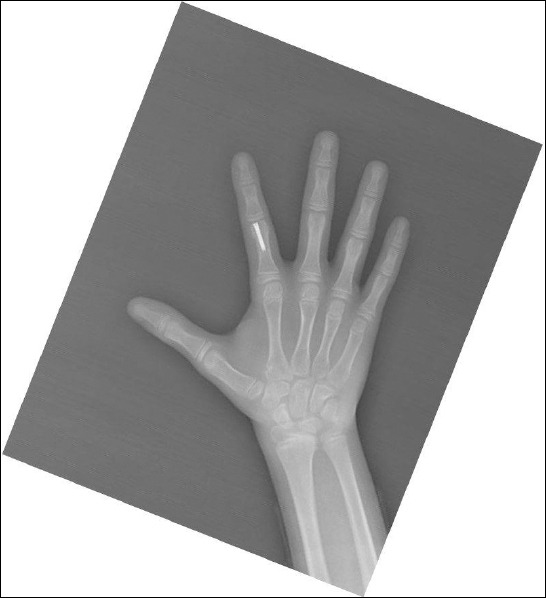

Background: This prospective case series aimed to evaluate the short- to medium-term radiological and clinical outcomes of intramedullary screw (IMS) fixation in pediatric patients with extra-articular proximal phalanx fractures.

Methods: Eleven patients (eight boys and three girls) aged 5-15 years underwent IMS fixation between January 2020 and June 2022. Antegrade or retrograde techniques were used depending on the fracture location. Postoperatively, patients were immobilized with finger splints for 3-5 days, followed by home exercises and physiotherapy. Bone union and functional status were assessed at one and four weeks after rehabilitation. Patient satisfaction, union status, and finger range of motion were also evaluated. Satisfaction outcomes were categorized as excellent, good, fair, or poor.

Results: The mean patient age was 9.4 years (range: 5-15), and the mean follow-up period was 29.1 months (range: 24-36). The right hand was affected in eight cases, the left hand in three cases, and the dominant hand in eight cases. Fracture distribution included four neck, four shaft, and three base fractures. The mechanisms of injury included ball-related trauma (n=5), falls (n=3), crush injuries (n=2), and punching (n=1). The average time from injury to presentation was 2.5 days (range: 0-9). Seven patients underwent surgery using the retrograde fixation technique, while four patients underwent surgery using the antegrade fixation technique. Fracture union was observed within the first month in nine patients and was complete by the end of the second month in two patients. At the last follow-up, the range of motion of the metacarpophalangeal, proximal interphalangeal, and distal interphalangeal joints of the operated finger was assessed. Deficits of 1.8 (range: 0-10), 2.7 (range: 0-10), and 0.9 (range: 0-10) were observed when compared to the contra-lateral side, respectively. Ten patients demonstrated excellent outcomes, while one patient exhibited a good outcome.

Conclusion: The intramedullary screw technique offers significant advantages in the surgical management of pediatric proximal phalanx fractures, particularly in rural areas with low socioeconomic status. This approach eliminates the need for pin-bottom fixation with a K-wire, significantly reduces hospitalization and additional treatment requirements, and minimizes the adverse impact of familial factors on the therapeutic process.